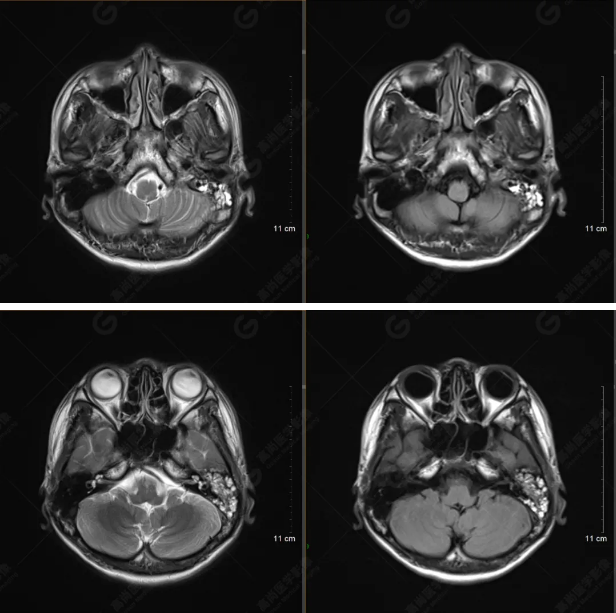

以下是平掃T2WI及FLAIR序列:

雙側(cè)大腦半球?qū)ΨQ,灰白質(zhì)對比正常,顱內(nèi)未見異常信號影。腦室系統(tǒng)未見擴(kuò)大,中線結(jié)構(gòu)居中。腦溝、裂未見增寬。幕下小腦、腦干未見異常。矢狀位示垂體形態(tài)、大小級信號未見異常。所示左側(cè)乳突內(nèi)見多發(fā)短T1長T2信號影。

顱腦MRI平掃未見明顯異常,左側(cè)乳突內(nèi)積血,建議補(bǔ)充SWI檢查。(左側(cè)為薄層原始圖像,右側(cè)為后處理5mm圖像)